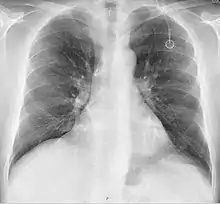

Повторна рентгенограма органів грудної клітки може негайно виявити ускладнення, пов'язані з процедурою. Це можуть бути пневмоторакс, гемоторакс або неправильне положення катетера.

- Пневмоторакс: Спроби отримати доступ до підключичної вени або яремної вени можуть травмувати легеню, потенційно спричиняючи пневмоторакс. Якщо пневмоторакс досить великий, можливо, потрібно буде встановити грудну трубку. У досвідчених руках частота цього ускладнення становить близько 1 % при встановленні через підключичну вену. При встановленні через яремну вену шанс пневмотораксу практично відсутній.